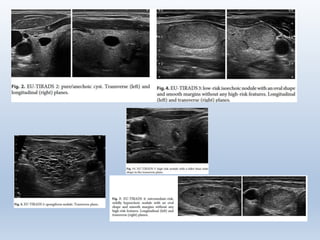

Échographie thyroïdienne

• Chaque nodule de la thyroïde est décrit selon la classification

EU-TIRADS (5 niveaux).

• Chaque nodulede la thyroïde est décrit selon la classification EU-TIRADS (5 niveaux). • Les autres imageries (scanner, IRM) relèvent du spécialiste (goitre plongeant, compression trachéale ou œsophagienne, rapports vasculaires).